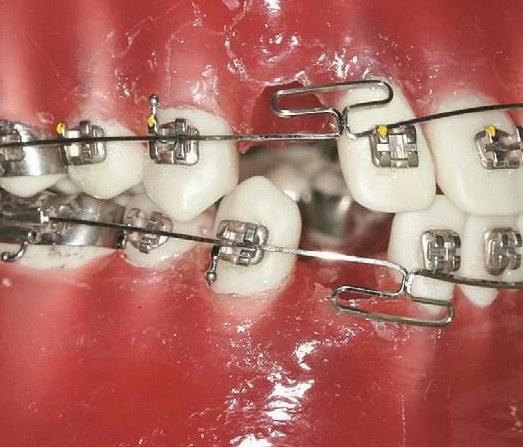

弯制垂直曲

垂直曲是MEAW弓的核心结构,需严格控制高度、宽度和圆弧度:

- 高度:通常为7-8mm,需根据牙齿移动距离调整(如压低后牙时高度可适当增加至10mm);

- 宽度:3-4mm,确保曲部与托槽间有足够空间(≥1mm),避免结扎时压迫牙龈;

- 弯制方法:

- 用细丝弯钳夹住标记点,将弓丝向龈向弯制U形垂直曲,顶部圆弧光滑(避免尖角刺激软组织);

- 用三叉钳调整曲的两侧臂,使其与牙长轴平行,确保曲部受力时能均匀传递力量;

- 重复操作弯制所有垂直曲,检查曲的高度、宽度及对称性。